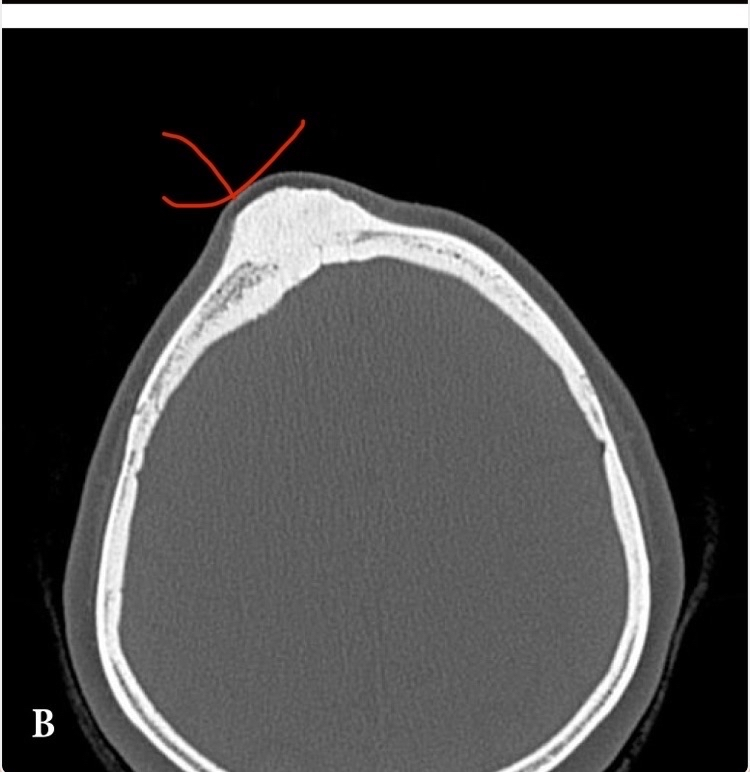

For example, in a case of a 35-year-old woman who experienced a severe blow to her frontal bone, what happened? As expected, a subperiosteal hematoma formed, then ossified into a large bony mass. Interestingly, the growth continued even after several years. The exact scientific explanation for the continued bone growth after years from the injury is unclear, but it may be an exaggerated protective response by the body (see figure 5) [34].

(Figure 5: a prominent bony mass at the injury site formed years after ossification of the subperiosteal hematoma)